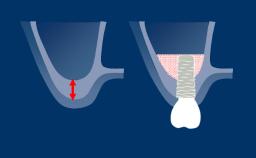

Timing of Implant Placement after Tooth Extraction

Immediate Restoration and Loading

Ridge Preservation Techniques